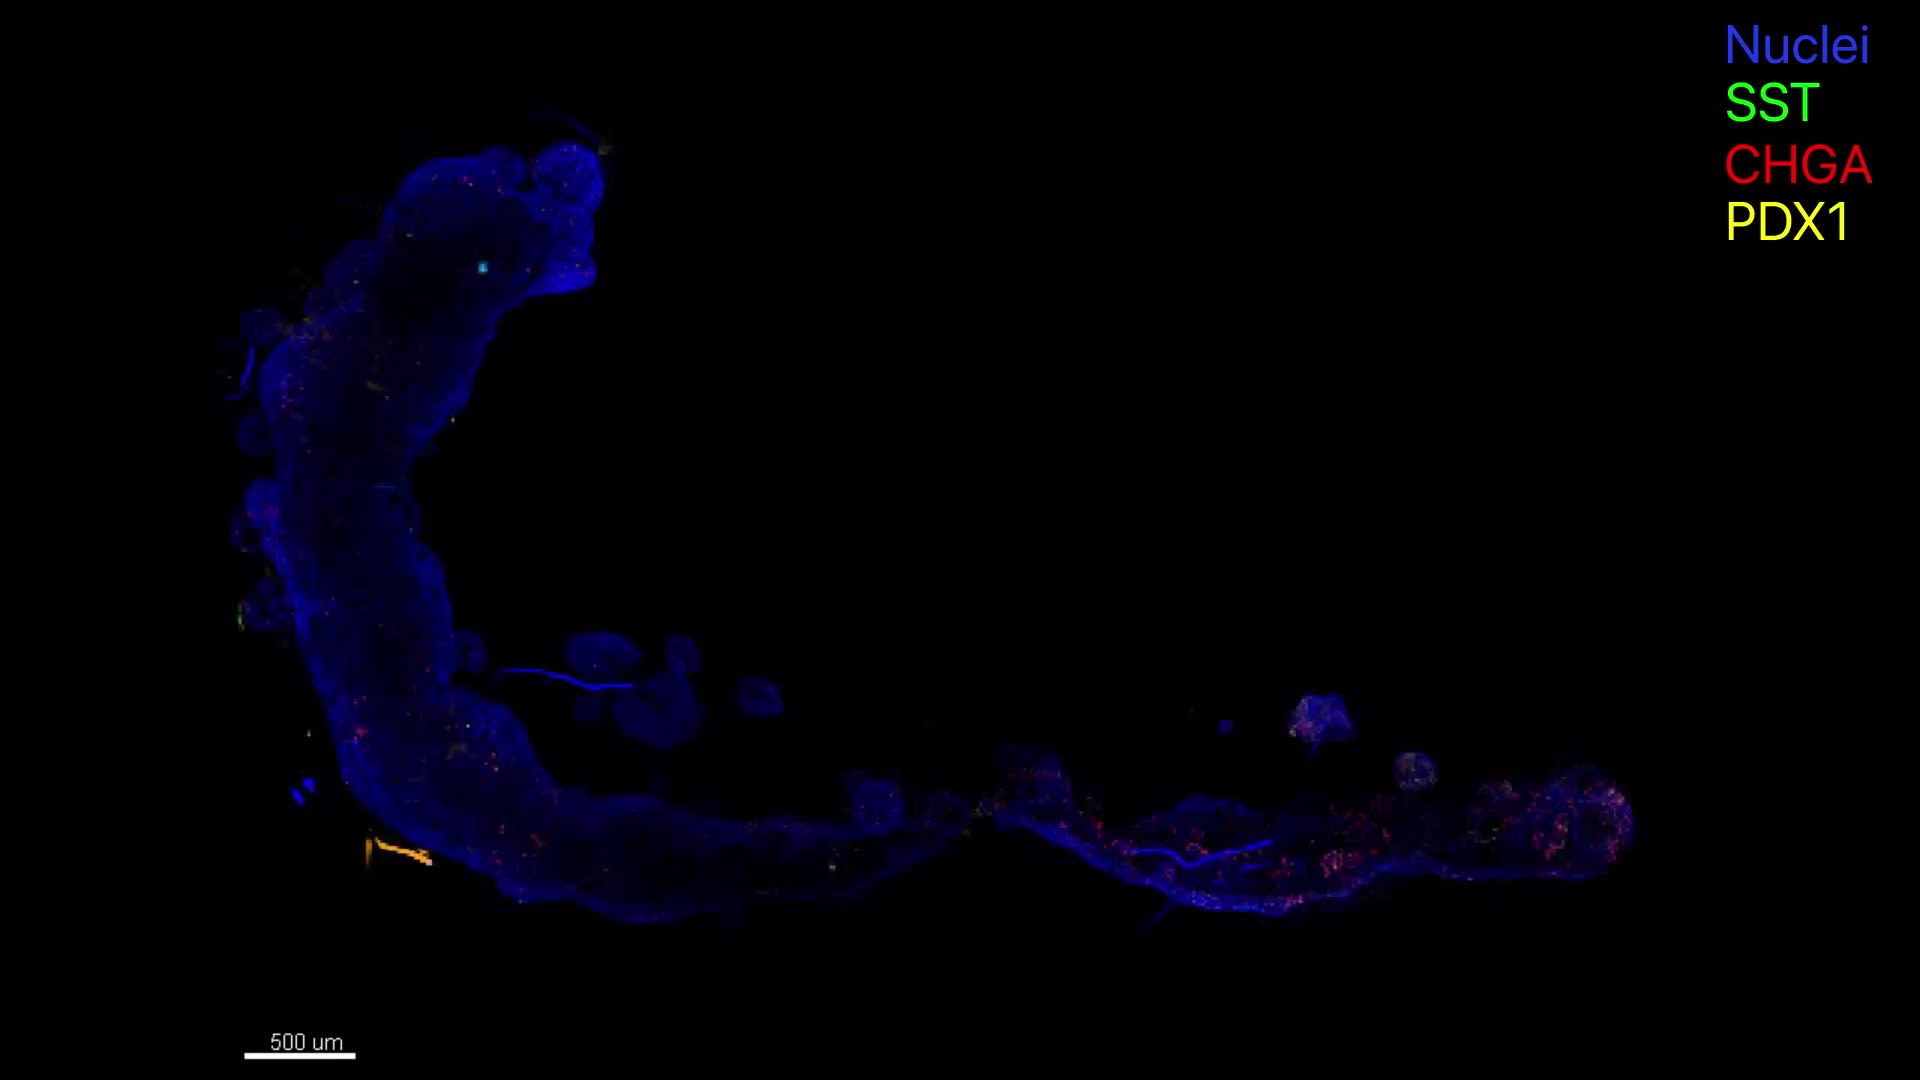

An immunofluorescence video showing the multiregional mini‑stomach model in action. Credit: B. Jones, G. Benedetti et al., Nature Biomedical Engineering.

- each region of the mini-stomach retained the characteristics of its original stomach area

- the different regions communicated with each other, as they do in the human body

- the models were able to produce stomach acid, a key function that is often disrupted in rare gastric diseases.